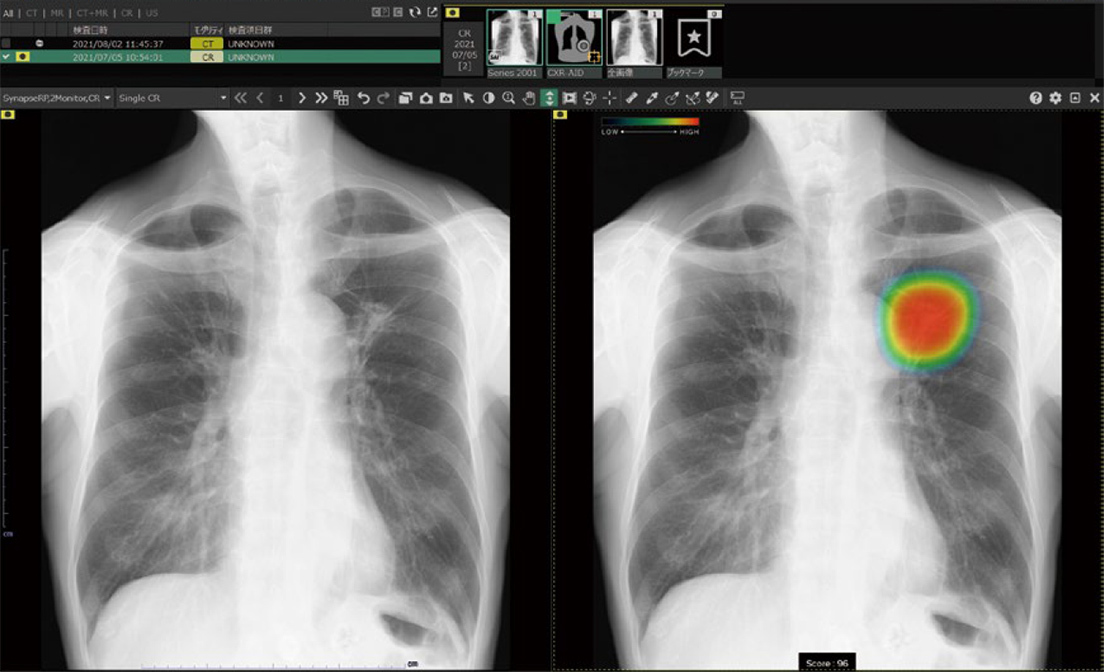

CXR-AIDは、胸のレントゲン写真をAI(人工知能)が自動で解析し、病気のサインを見つけるために医師をサポートするシステムです。

肺の中にある影(けっせつや炎症、空気のたまり など)をAIがチェックし、「異常の可能性がある部分」を画面上にわかりやすく表示します。

これにより、医師がより正確に・早く診断できるようになります。